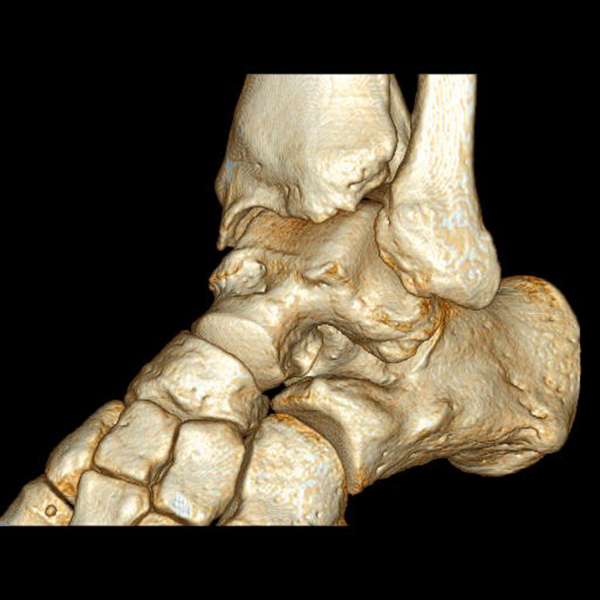

Supramalleoläre Korrektur-Osteotomien

Patienten mit frühen Stadien einer Arthrose am Sprunggelenk sollten auf mögliche bestehende Achsabweichungen hin untersucht werden. Valgus- oder Varus-Deformitäten des Rückfußes und des Unterschenkels zeigen pathologisch veränderte Druckverteilungsmuster insbesondere im OSG, was langfristig zur Entwicklung einer asymmetrischen Sprunggelenks-Arthrose führt 116.

Korrektur-Osteotomien können die normale Biomechanik des OSG wiederherstellen und damit den degenerativen Prozess aufhalten bzw. verlangsamen 117.

Die supramalleoläre Osteotomie ist ein gelenkerhaltendes Verfahren, das der Behandlung des exzentrischen Knorpelverlustes infolge einer übermäßigen Varus- oder Valgusfehlstellung vorbehalten ist. Der Grad der supramalleolären Fehlstellung hat einen signifikanten Einfluss auf die Kraftübertragung auf die Gelenkoberfläche 119. Die daraus resultierende fokale statische und dynamische Überlastung im Gelenk führt zu einer raschen Degeneration der Gelenkoberfläche 116120.

Supramalleolare Osteotomien werden durchgeführt, um die mechanische Achse neu auszurichten und so die Belastung im Sprunggelenk neu zu verteilen, mit dem Ziel, die degenerative Kaskade zu verzögern oder zu stoppen 118121122

Indikationen für eine supramalleoläre Osteotomie sind asymmetrische Valgus- oder Varusarthrosen mit mindestens 50% erhaltener tibiotalarer Gelenkoberfläche. Kontraindikationen sind ältere Patienten mit einer Instabilität des Rückfußes, die durch eine Bandrekonstruktion nicht behoben werden kann, Patienten mit schweren vaskulären oder neurologischen Erkrankungen der betroffenen Extremität, entzündlichen Arthritiden und aktive Infektionen.

Zur Vollansicht und zum Lesen der Bildbeschreibung bitte das Bild anklicken.